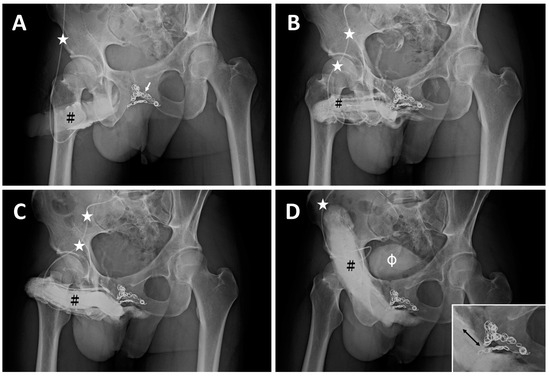

| ED a | 2008 | Early detumescence of rigid erection, position-dependent | A multiplanar diagnosis workup showed a veno-occlusive dysfunction. |

| CE(I) b | 2010 | Same | Acute chest pain was caused by the migration of a dumbbell-shaped coil to the right pulmonary artery. |

| CE(II) c | November 2012 | Same | A tapeworm-shaped coil was noted in the region of the right iliac vein at 90 degrees to the venous channel. |

| CE(III) d | May 2014 | Same | A pigtail-shaped coil was shown at the left internal pudendal vein level at 90 degrees to the venous channel. |